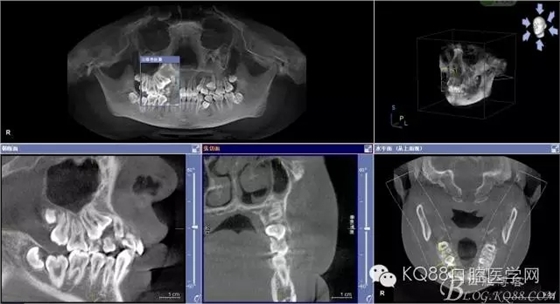

患者、女、15歲,主訴:右側(cè)前磨牙未萌出,要求口腔檢查。正畸科經(jīng)過臨床檢查,建議拔除14、24、34、44、54、55、65、74,然后做正畸治療。cbct檢查:14高位埋伏于15、13之間,拔除難度較大,遂術(shù)前與患者家長溝通,講明拔除14可能存在的臨床風(fēng)險(xiǎn),患者同意手術(shù)方案,簽知情同意書。

圖2.術(shù)前cbct檢查:54、55乳牙滯留,14、15埋伏阻生,14位于15的上方。

圖5.水平剖面觀:14牙冠緊鄰15與13牙根之間,要求分牙一定要小心謹(jǐn)慎